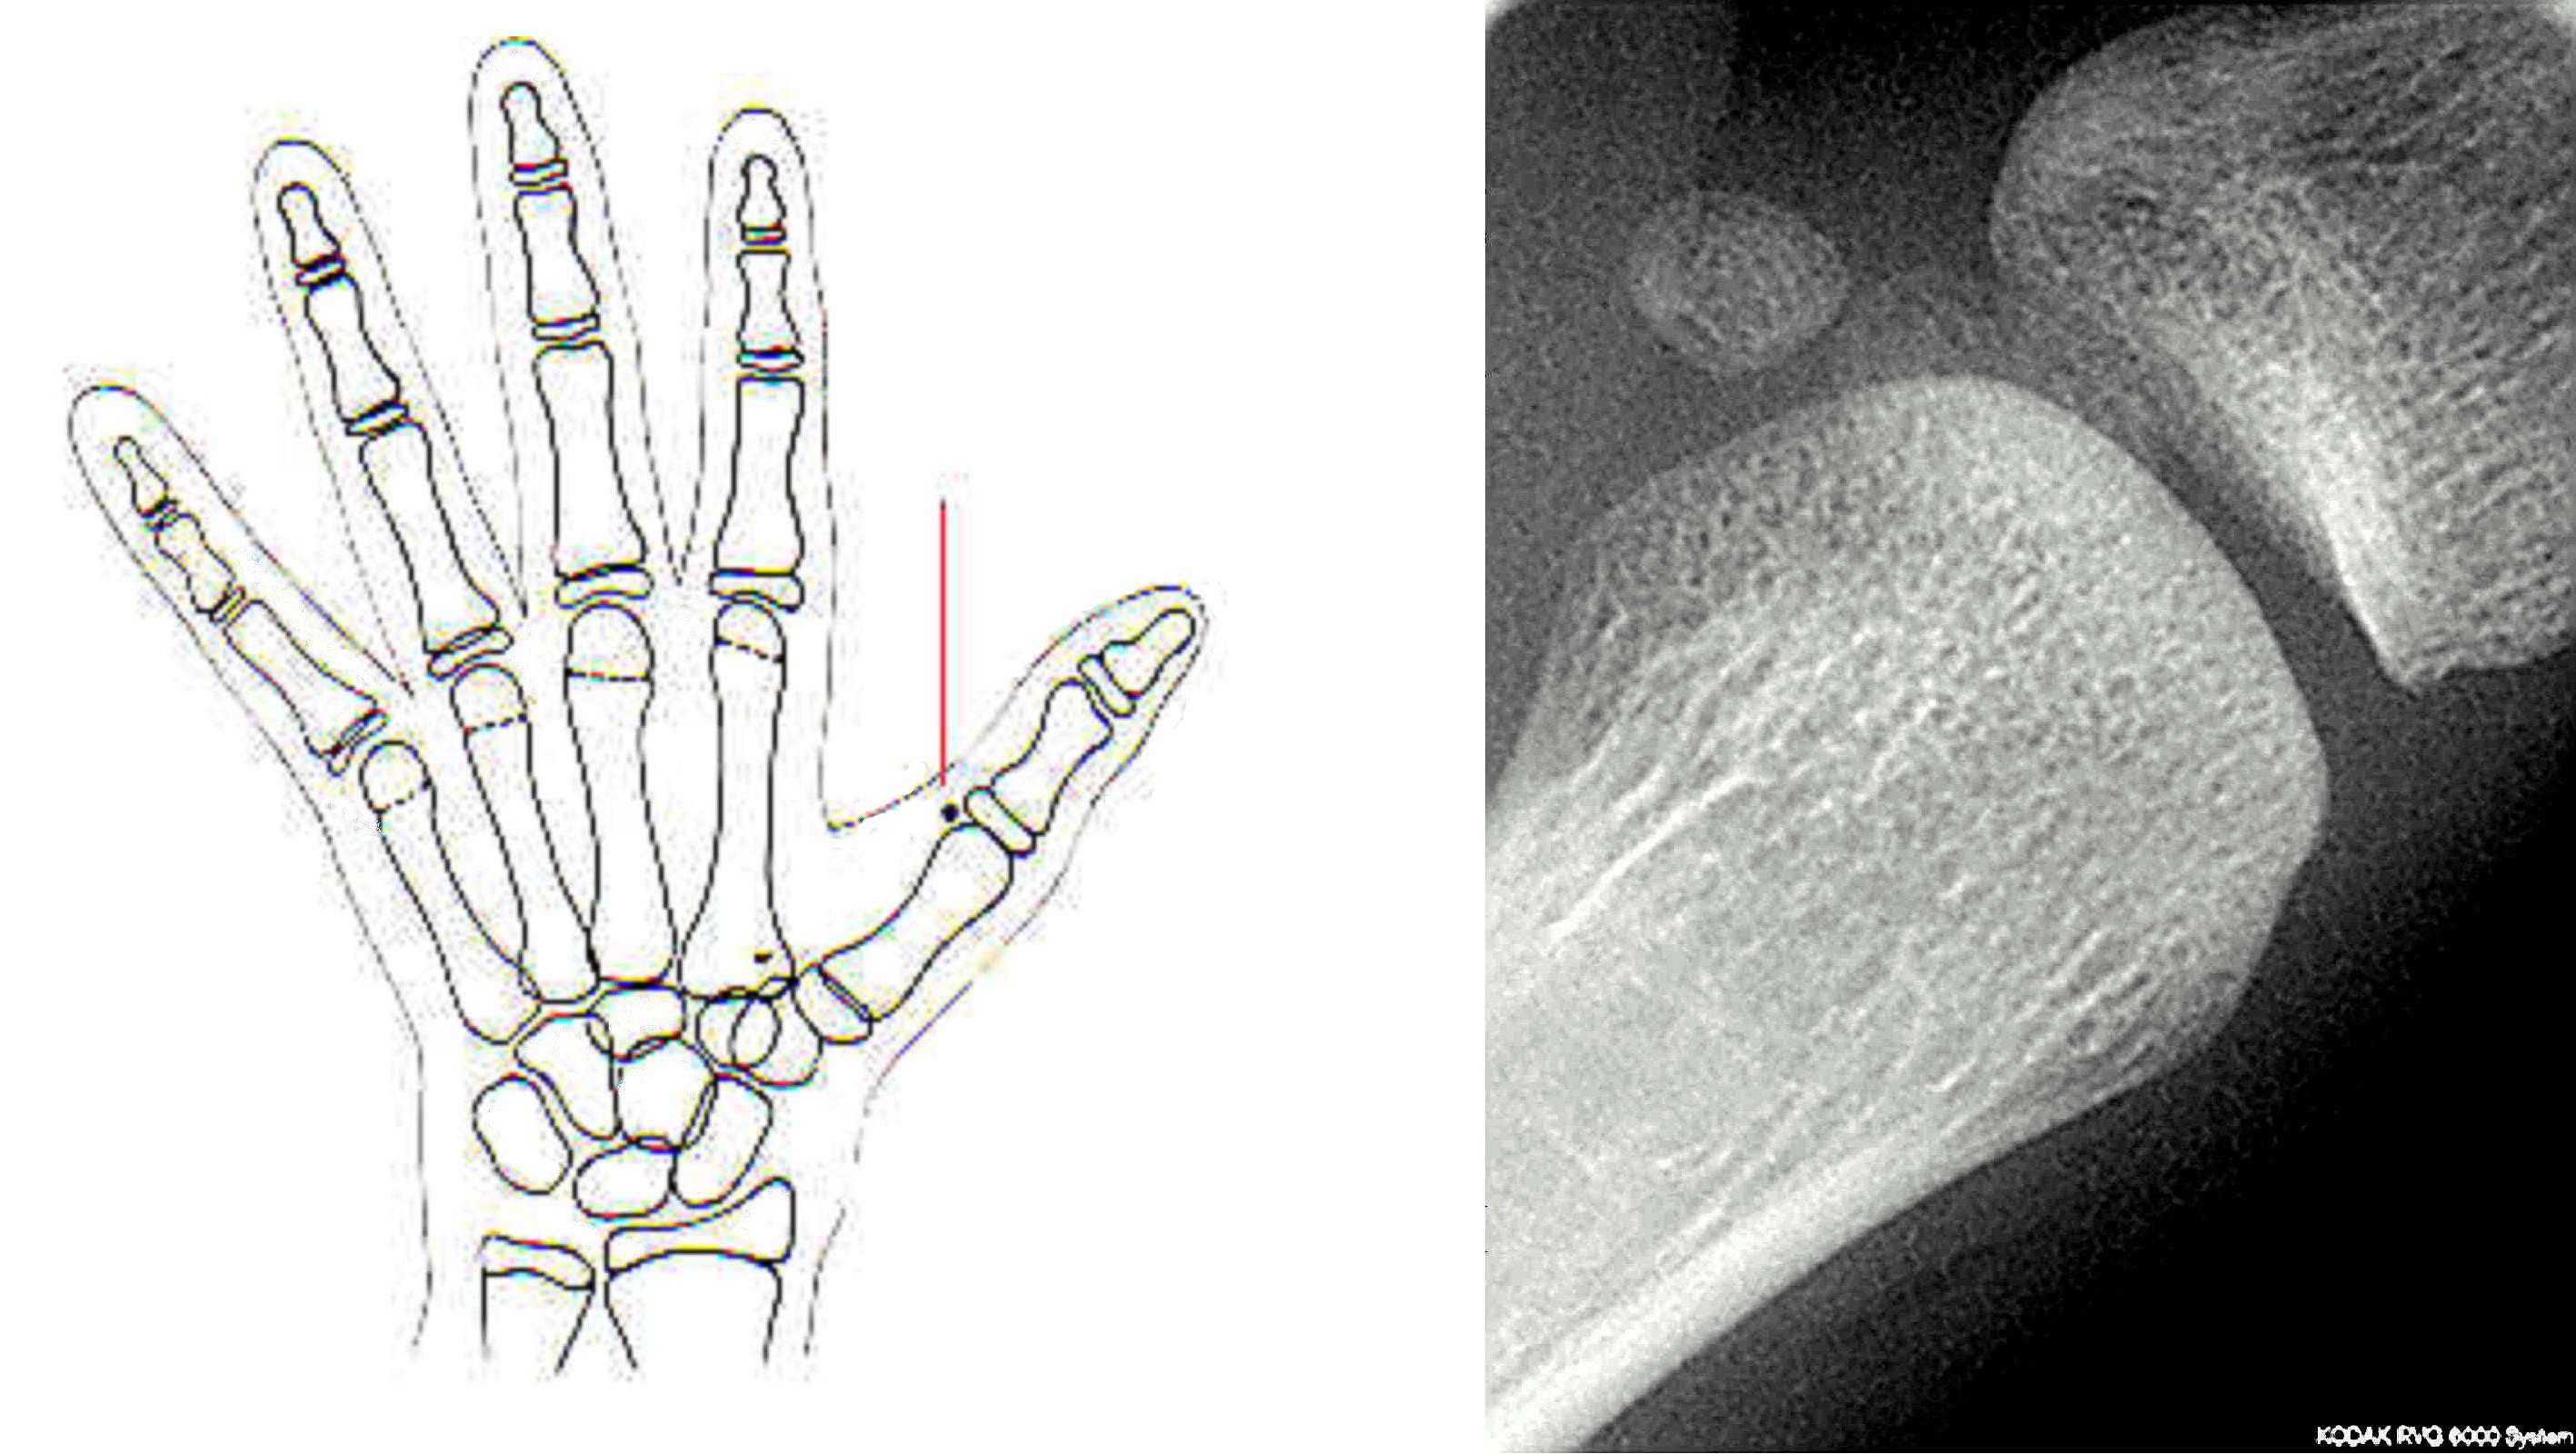

Radiographie de la main

Sésamoïde du pouce

Os sésamoïdes médial et latéral situés au niveau de l'articulation métacarpo-phalangienne du pouce. (Source : Wikipédia. Os sésamoïde [Internet]. Wikipédia; 2010.)